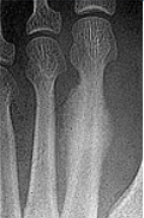

| What type of fracture is this? | Greenstick fracture (common in paediatric patients) |

| Describe what the arrows are showing | Torus fracture of the 1st met. "Buckling" of the proximal one third diaphysis is seen both medially and laterally. Common in paediatric patients |